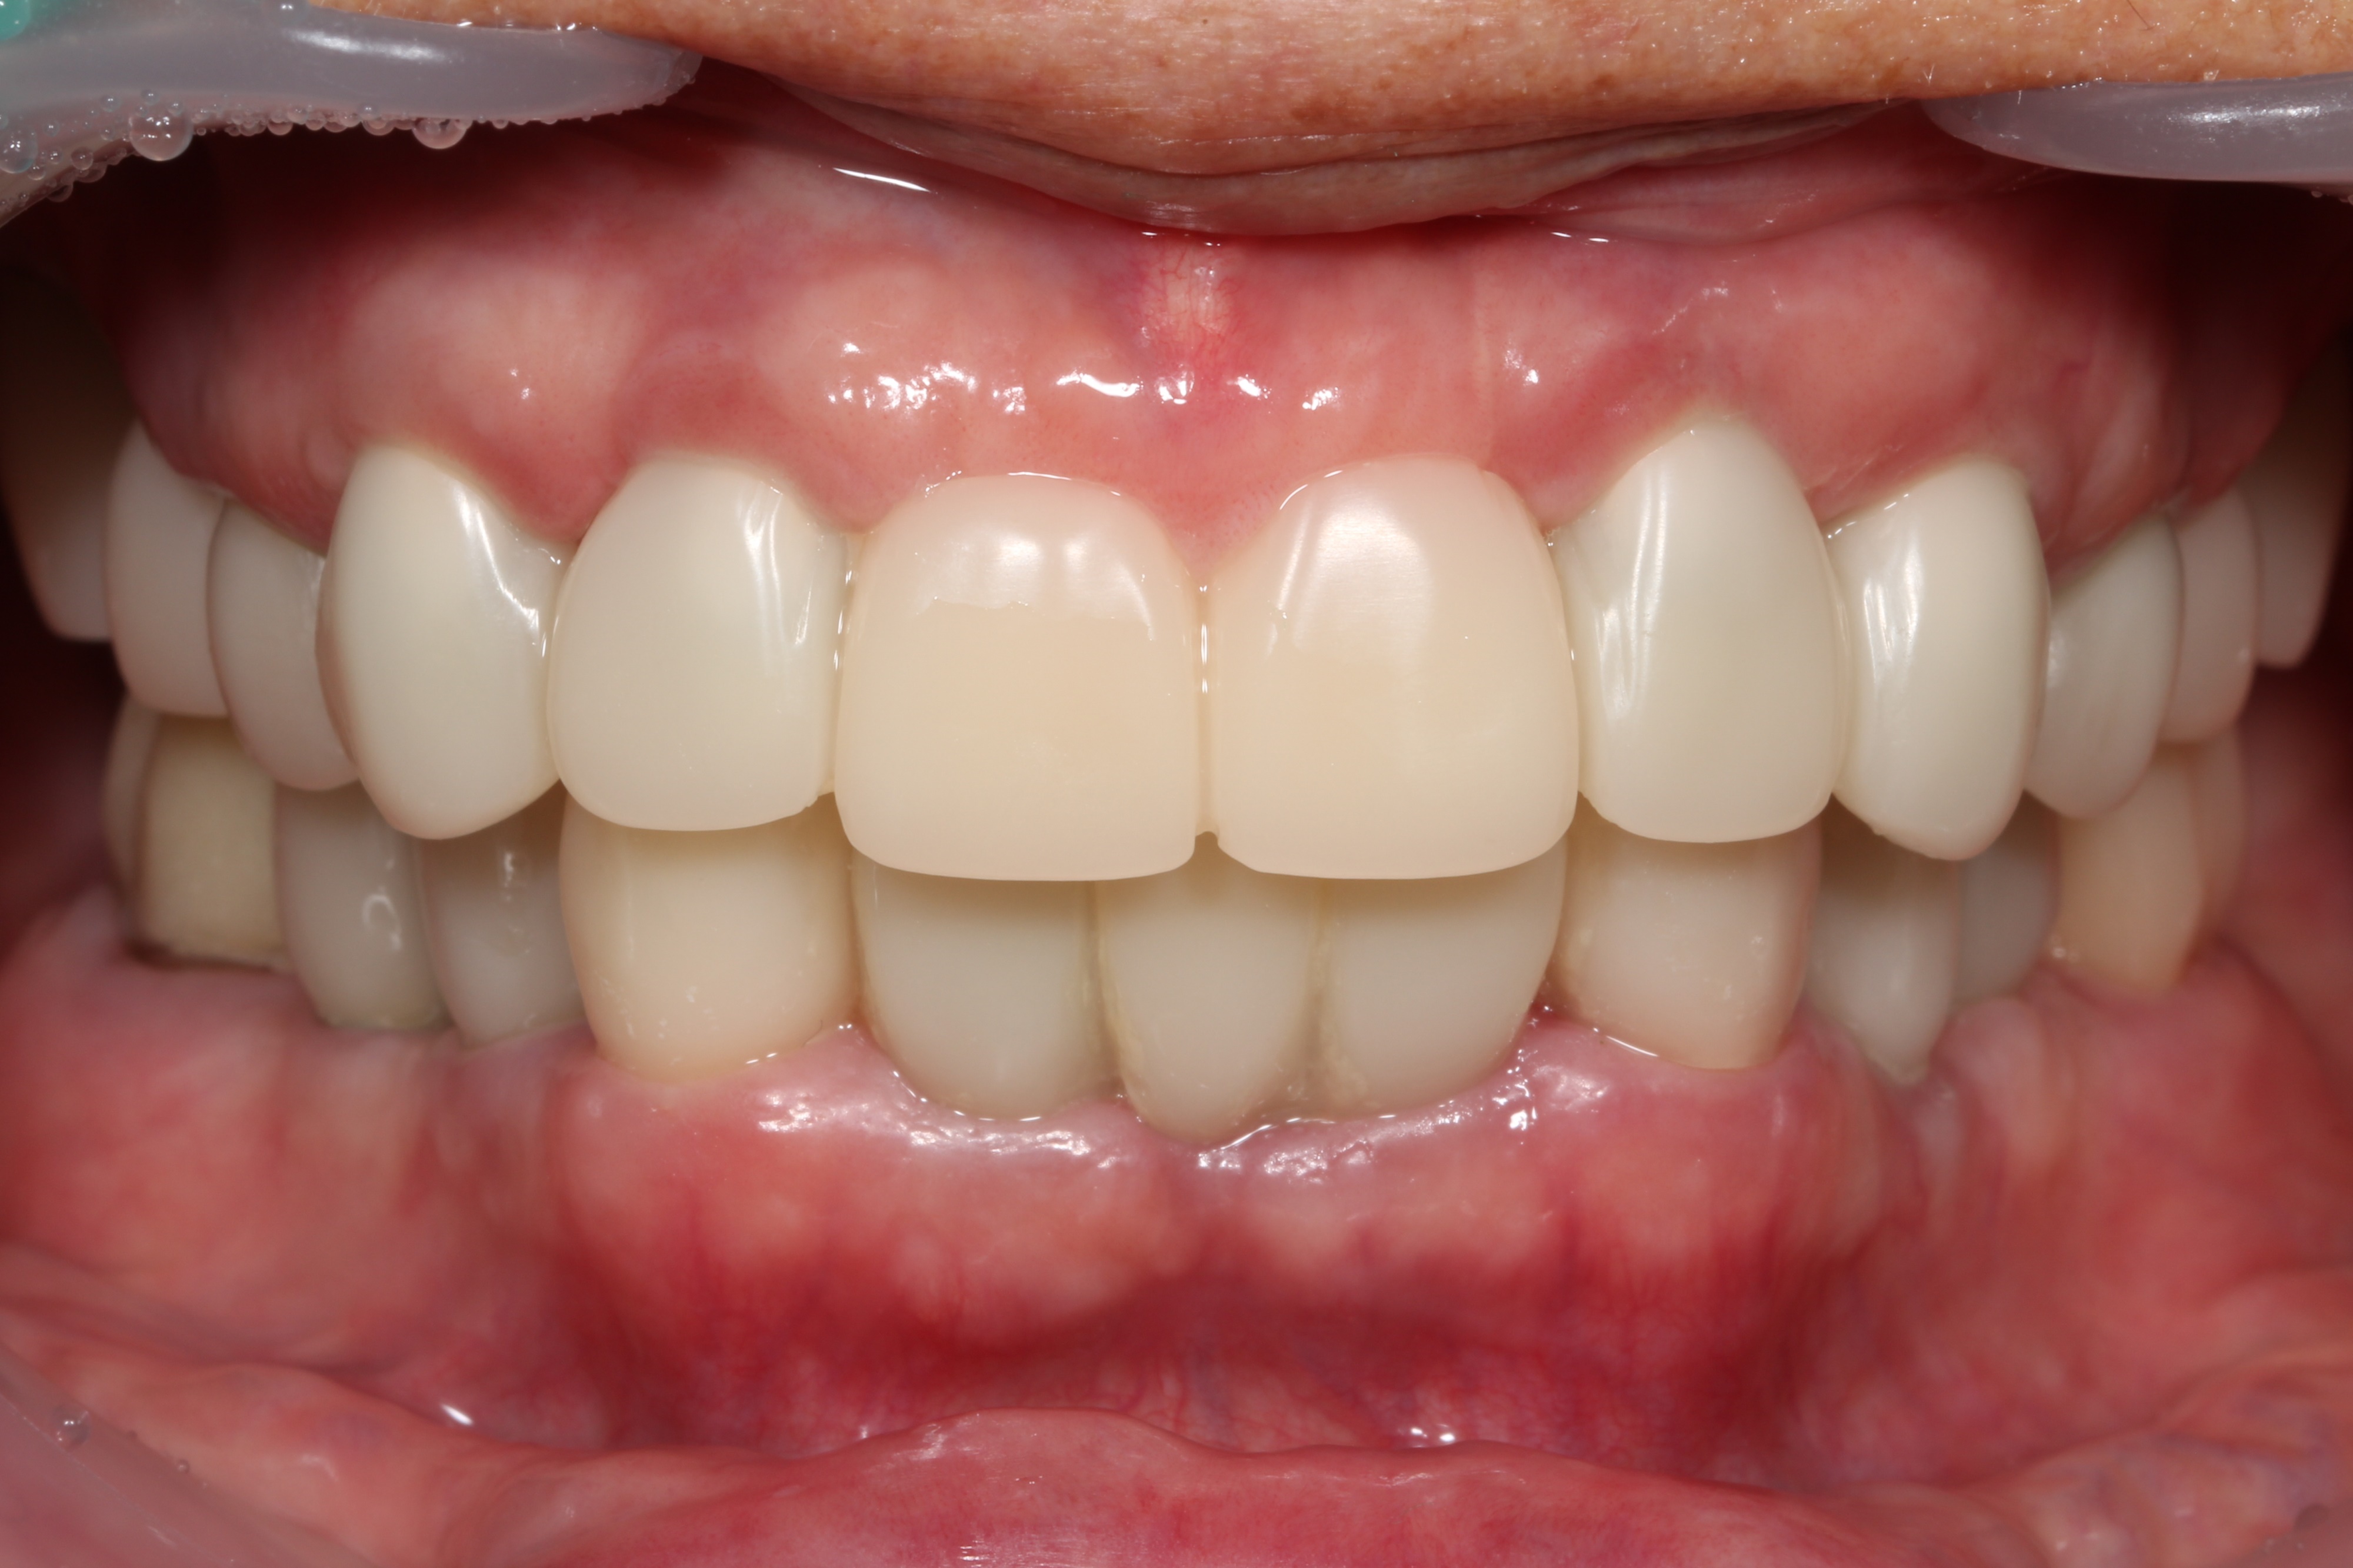

치료 후 임상사진

지르코니아 최종보철물 장착한 모습입니다.